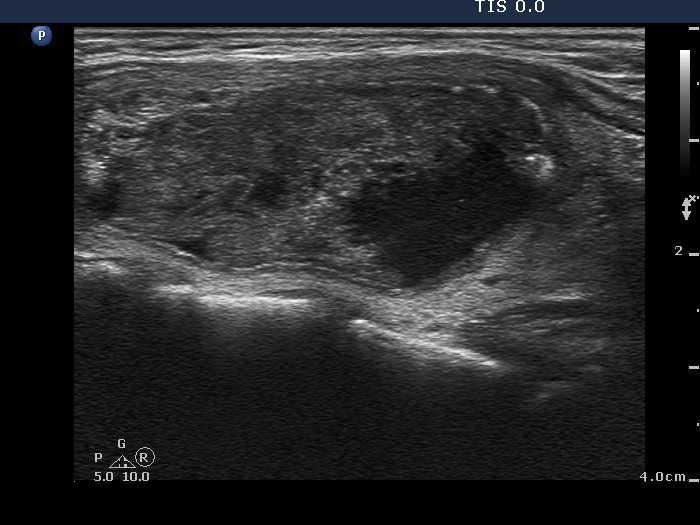

Ethanol sclerotherapy: other examples - Case 3: treatment of a gelatinous thyroid cyst

Third session of therapy (ultrasonographic picture 2)

Right lobe, longitudinal scan.